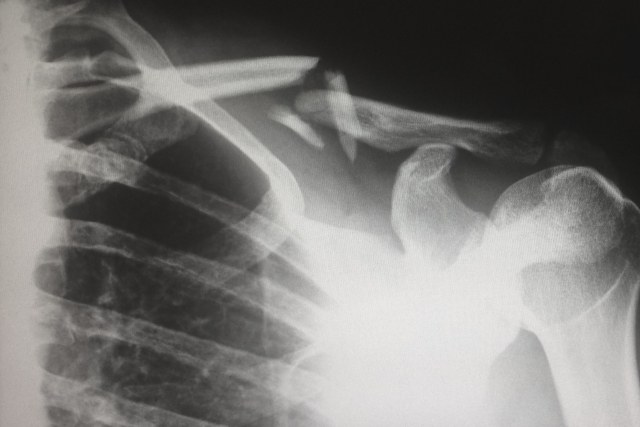

Finanziato nell’ambito del Programma operativo regionale del Fondo europeo di sviluppo regionale (POR-FESR) dell'Emilia-Romagna, il progetto permetterà di testare l’attività in vitro di biomateriali medicali su vari modelli cellulari. L’attività antitumorale viene valutata su linee cellulari tumorali di neoplasia della mammella e renale, mentre l’attività rigenerativa è studiata "seminando" sui dispositivi cellule ossee come gli osteoclasti e gli osteoblasti. I test saranno considerati di successo se verrà dimostrata attività inibitoria verso le cellule tumorali e rigenerazione tissutale per l’azione sulle cellule di tipo osseo. Inoltre, i biomateriali medicati dello studio DINAMICA saranno testati su una casistica di campioni biologici umani di metastasi ossee in modo da poter valutare la validità terapeutica in un campione contenente sia cellule tumorali sia quelle del microambiente osseo.

Nel prossimo futuro, anche i device sviluppati nell’ambito di DINAMICA verranno integrati nella pratica clinica, inizialmente per una loro validazione e, in seguito, per il trattamento di pazienti con metastasi ossee direttamente in sala operatoria durante un intervento chirurgico o in sedute di radiologia interventistica.